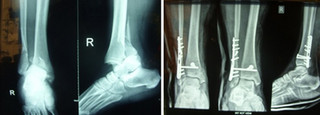

Η αντιμετώπιση ενός κατάγματος σφυρών, αμφισφυρίου ή τρισφυρίου (εάν έχει ξεκολλήσει κι ένα κομμάτι του πίσω τμήματος της κνήμης) είναι χειρουργική, ώστε να αναταχθεί το εξάρθρημα και να επανέλθει η ανατομική της άρθρωσης.

Διαφορετικά η άρθρωση θα οδηγηθεί σε αρθρίτιδα.

Μετά την εγχείρηση ο τραυματίας αποφεύγει την φόρτιση του σκέλους, αρχικά με νάρθηκα και δύο πατερίτσες για 2 εβδομάδες και στη συνέχεια χωρίς νάρθηκα, κάνοντας ασκήσεις για ακόμη 4 εβδομάδες.